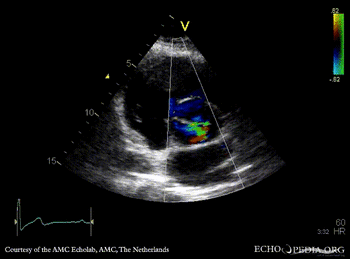

M-Mode through aortic root PLAX with Color Doppler: moderate aortic regurgitation